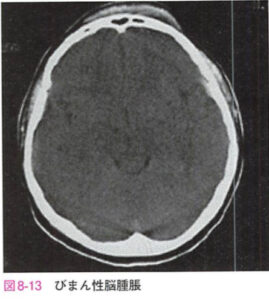

| びまん性脳腫脹 | 一次性脳損傷に加え、受傷早期の低血圧、低酸素血症、高二酸化炭素血症などによる二次性脳損傷が加わりびまん性脳腫脹が生じると考えられている。![]() |

|